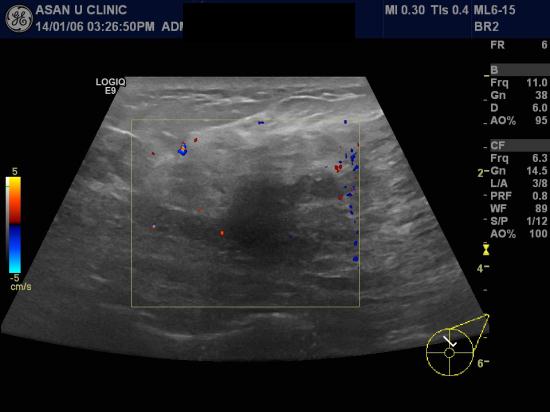

두달전부터 좌측유방이 뭉친것 같아 본원 내원한 28세 여성분입니다.

본원초음파상 좌측 유방에 3.9cm의 악성의심되는 혹과

겨드랑이의 림프절 비대가 확인되어

좌측유방의 혹 조직검사와 림프절 세침검사를 시행하였습니다.

좌측 유방의 침윤성 유방암과 액와부 림프절 전이암으로 결과가 나왔습니다.